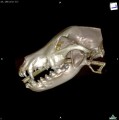

CT - angiografie (kočka)